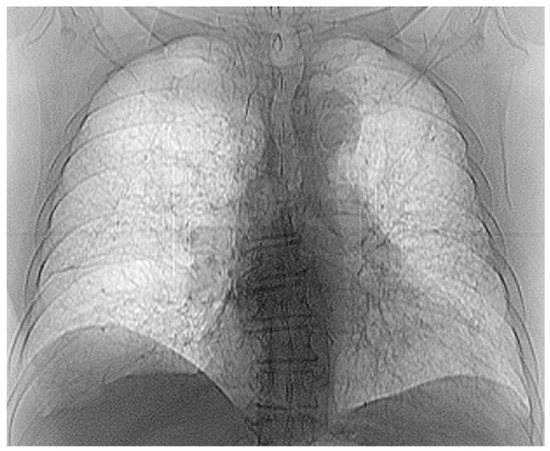

The chest radiograph of healthy lungs on which the fractal analysis was performed is shown in Figure 29a. Aside from the high-quality imaging provided by CT procedures (Figure 29a,b), the picture evaluation assured quantitative information regarding various structural features, such as the fractal dimension and lacunarity.

Figure 30 shows the 2D box-counting algorithm with the local fractal dimension calculation for the healthy-lung CT image. Figure 31 displays the 3D graphical representation of the voxels present in the CT lung image of healthy patient. Table 7 presents the calculated values for the fractal dimension and the lacunarity of the CT image evaluations for the healthy patient.

Table 7 shows the known fractal indicators, such as the fractal dimension of the CT image of the left lung, dHL = 1.6410 ± 0.3577, and lacunarity Λ = 0.0475; and the fractal dimension of the right lung, dHR = 1.6318 ± 0.3598, and lacunarity, Λ = 0.0486.

Figure 29. (a) Healthy lung image, (b) binary version, (c) mask for the left lung, (d) mask for the right lung.